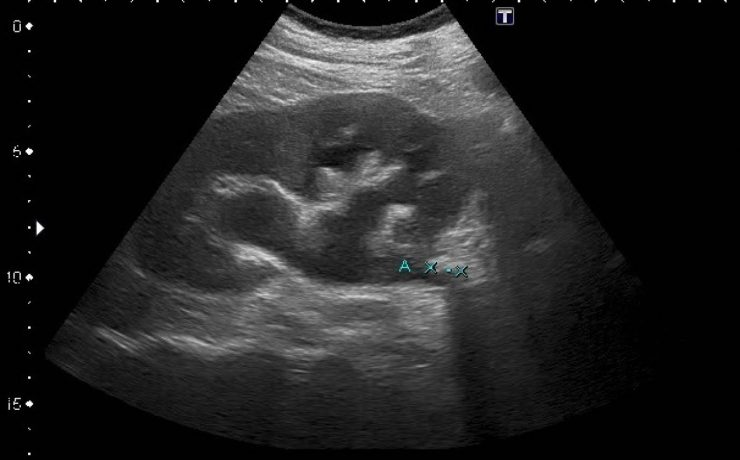

APENDICITIS DURANTE EL EMBARAZO

La apendicitis aguda durante el embarazo constituye la causa más frecuente de abdomen agudo quirúrgico no obstétrico, reportándose a nivel mundial una incidencia de 0.1 a 1.4 casos por cada 1,000 embarazadas. Algunos estudios en América Latina han reportado una incidencia aproximada de 1 por cada 1,200 embarazos. El diagnóstico